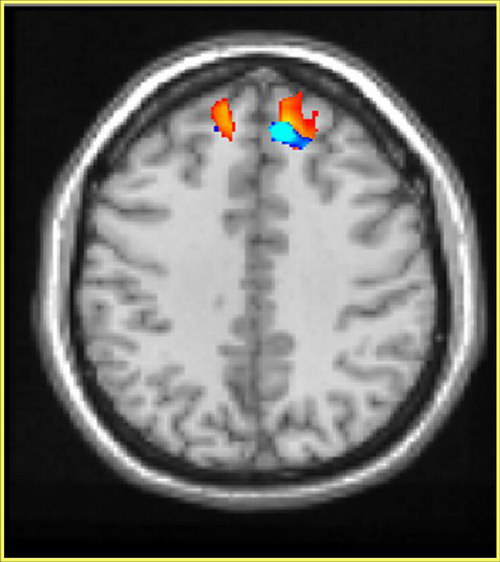

صورة إلكترونية للدماغ ونلاحظ نشاطاً في منطقة الناصية (اللون الأحمر). إن التجارب الجديدة التي أجريت بواسطة جهاز الرنين المغنطيسي الوظيفي تؤكد على الدور الكبير الذي تلعبه منطقة الناصية في السلوك العدواني وبخاصة لمدمني الخمر والمخدرات فتظهر عليهم علامات لسلوك عنيف تجاه الآخرين.